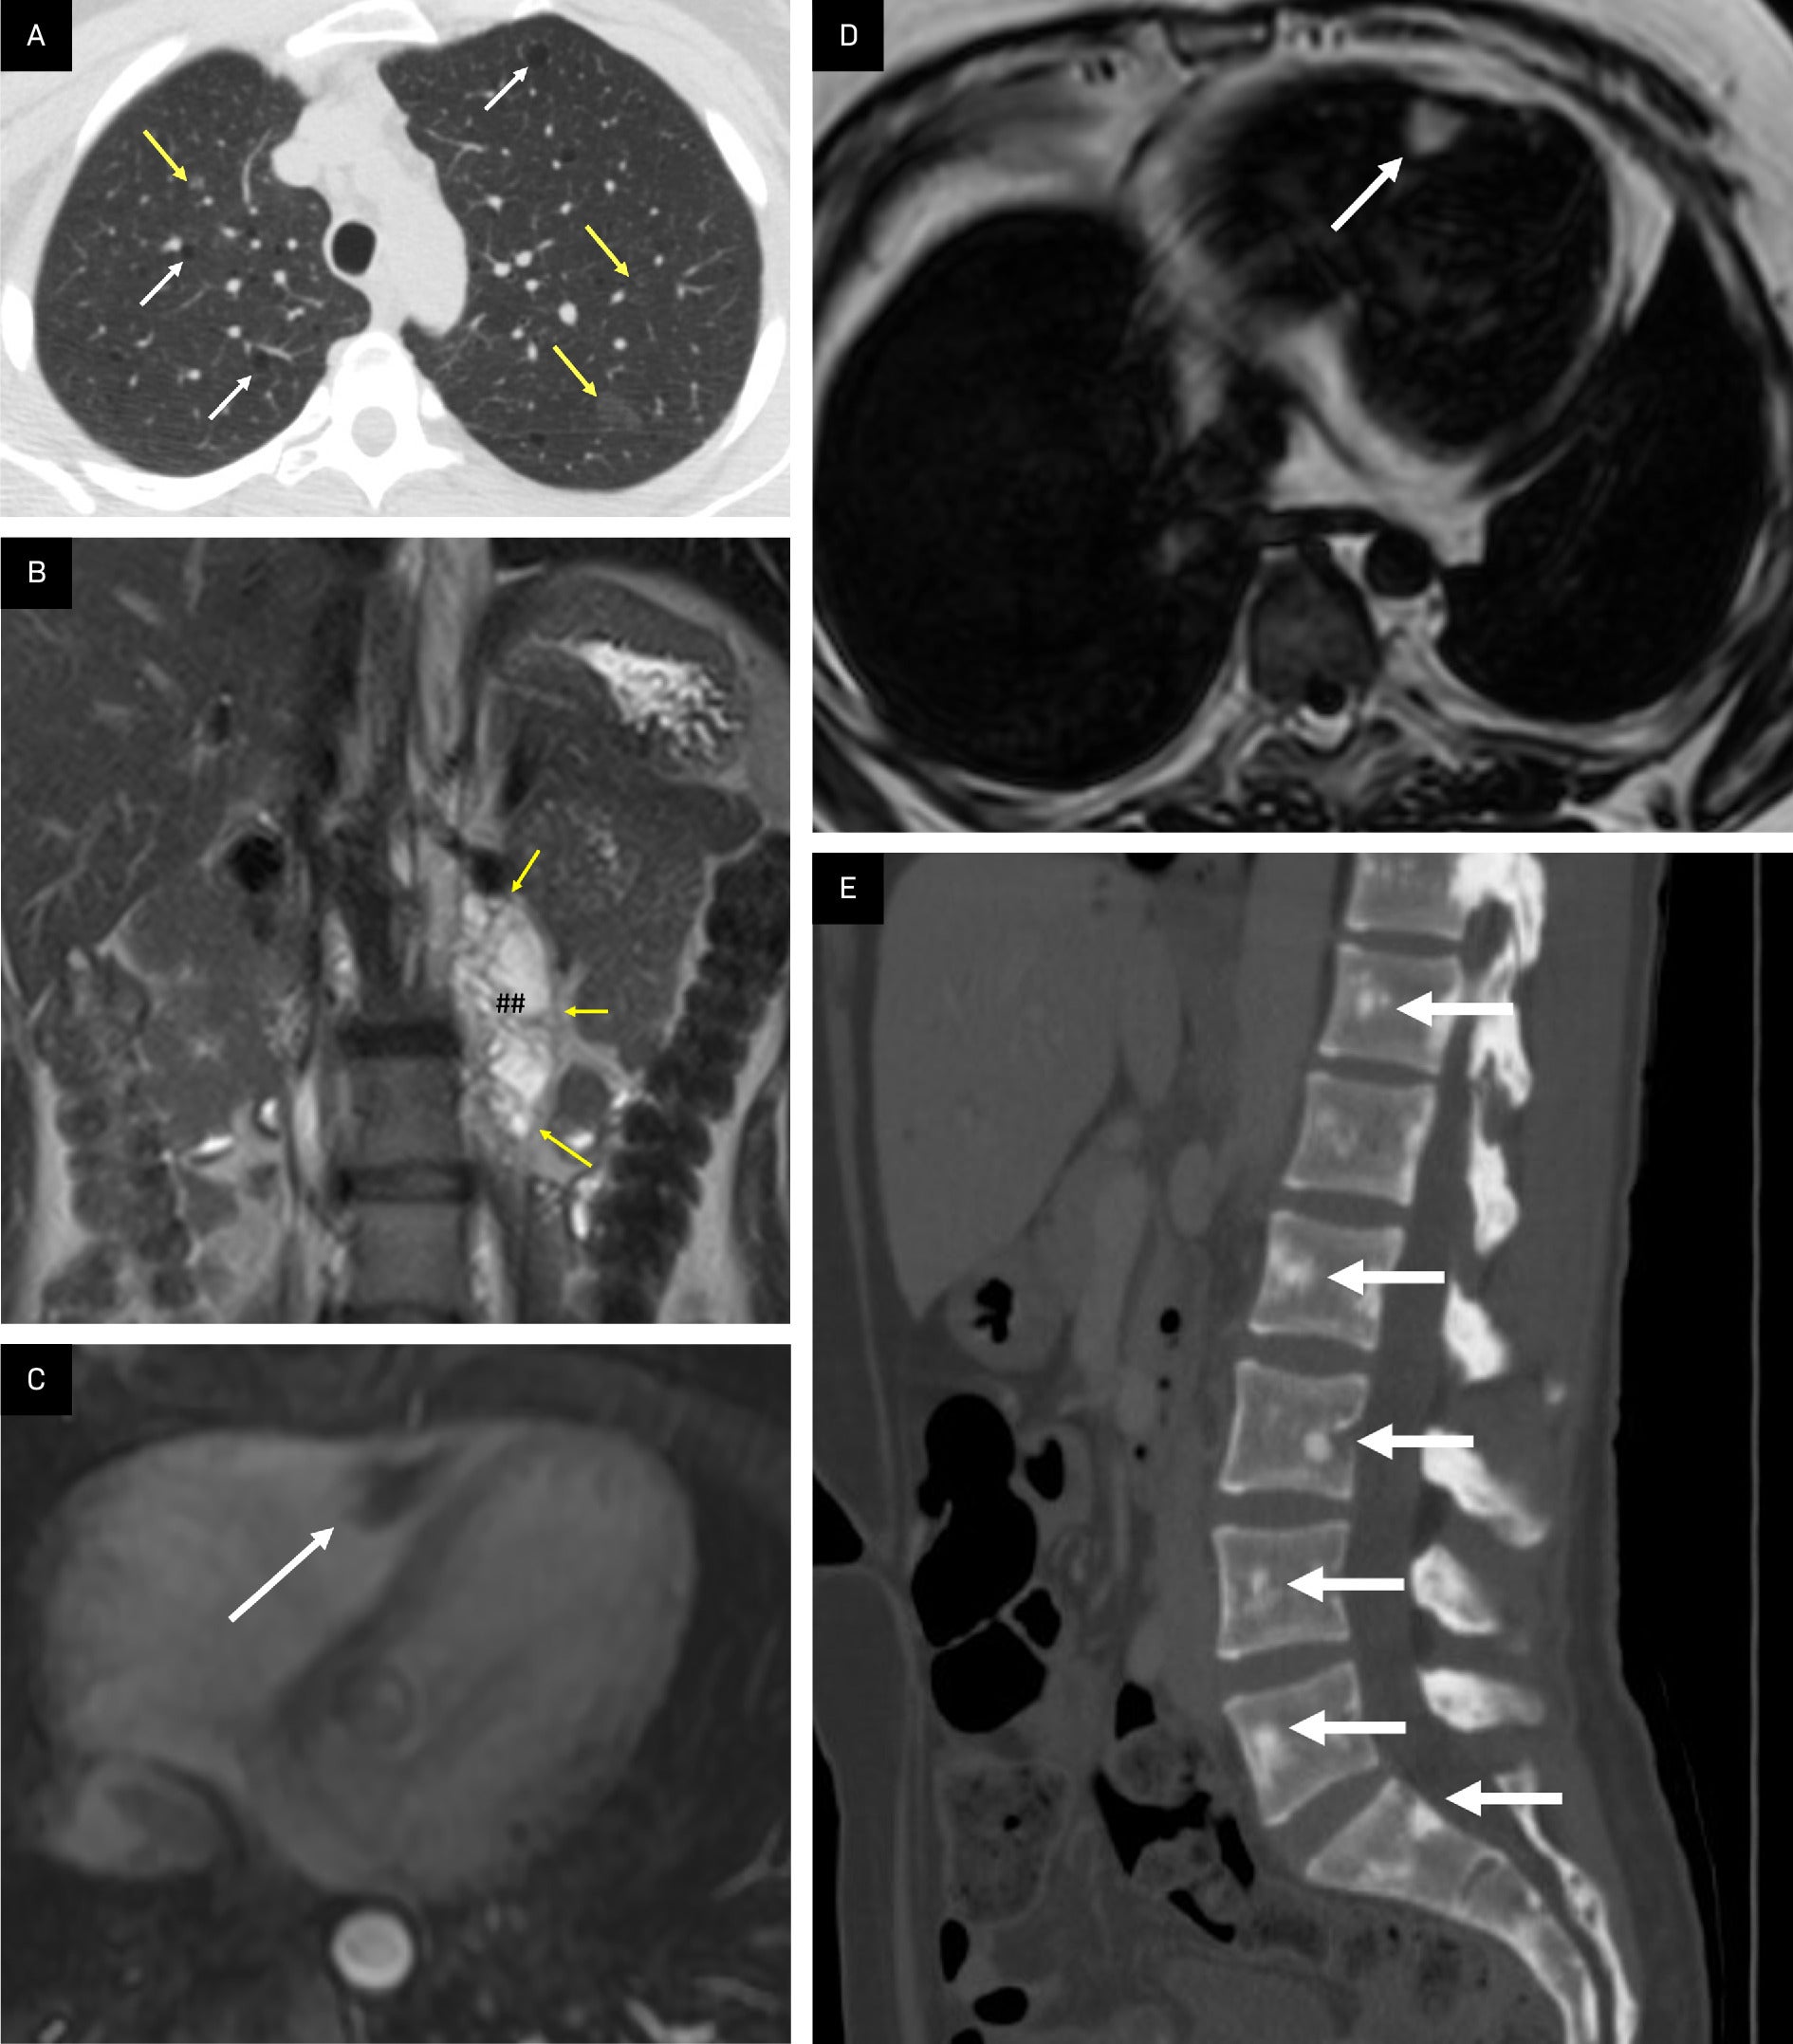

Understand Tuberous Breast Deformity, a congenital condition affecting breast shape and development. Learn about effective surgical correction options, breast augmentation procedures, and reconstruction techniques designed to restore a natural appearance. Discover expert insights on symptoms, treatment plans, and how plastic surgery can address this unique structural breast concern to help you achieve your desired aesthetic goals.